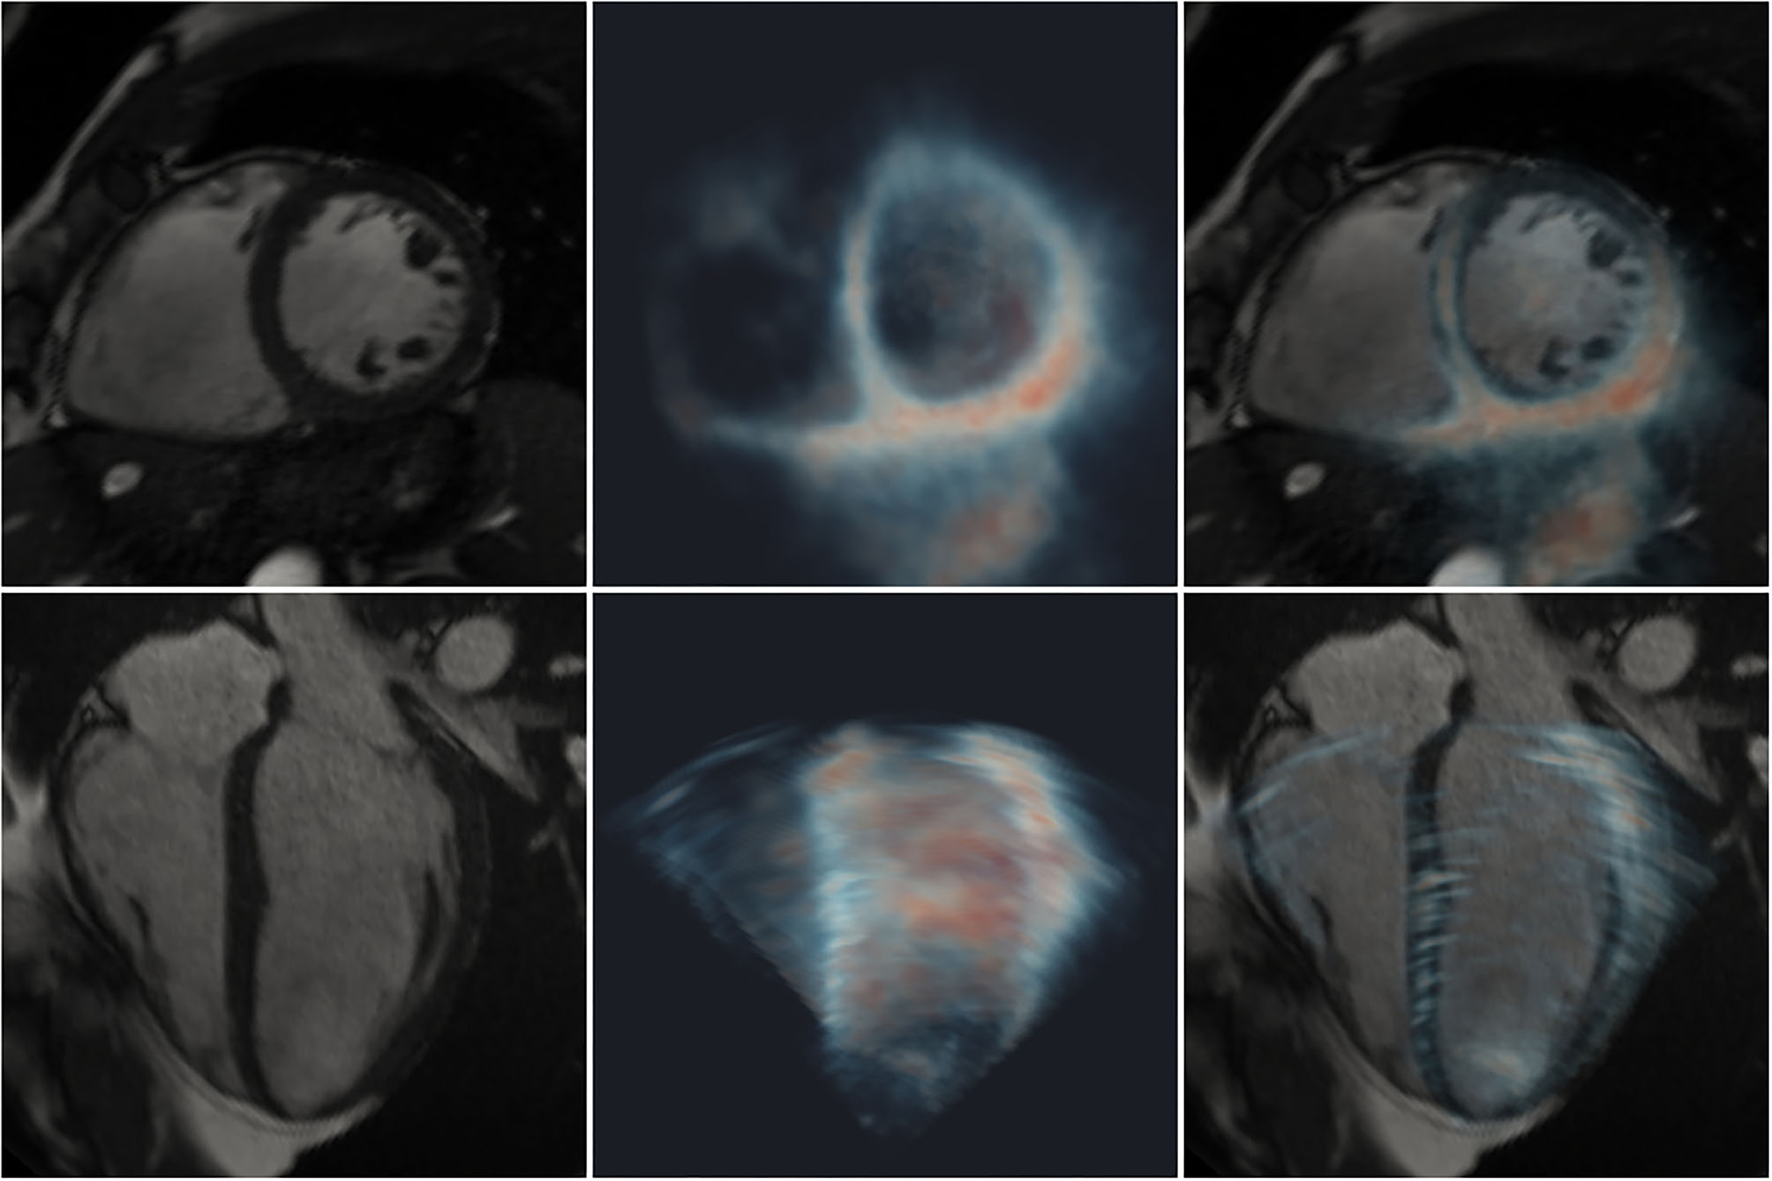

Figure 3

Registration of 2D CMR images (greyscale) with a 3D-echo image volume (maximum intensity projection using blue-to-red colormap). Short- (top row) and long- (bottom row) axis views are shown. Left: CMR; middle: 3D-echo; right: fused CMR and 3D-echo.

All cases exhibited good visual alignment of CMR and 3D-echo using the interactive rigid registration method. An example is shown in Figure 3, where variable signal intensity is seen across the 3D-echo image. Further examples showing the alignment at different stages during the cardiac cycle for additional subjects can be found in the Supplementary Videos 3–5.